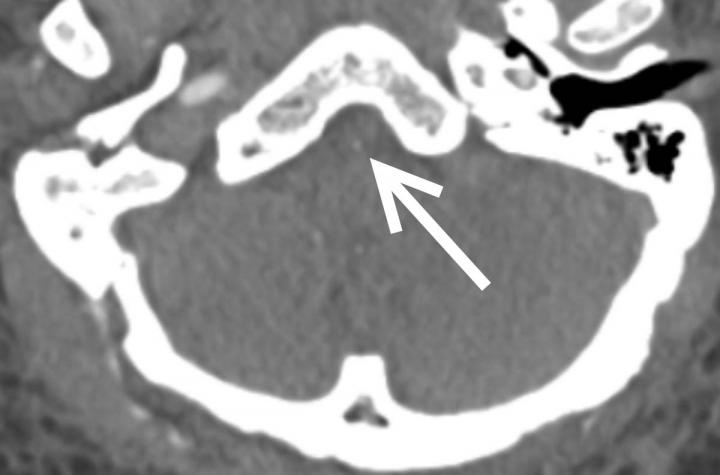

Out of 81 patients with brain scans, 18, or just over one in five, had findings that were considered emergency or critical, including strokes, brain bleeds and blocked blood vessels. At least half the patients had pre-existing histories of high blood pressure and/or type 2 diabetes. Three patients with emergent/critical findings died while admitted.

The exact mechanisms for COVID-19's harmful neurological effects are not known and may involve multiple factors, although a popular theory holds that inflammation associated with the infection is the primary culprit. In the study, blood markers of inflammation were high in people with critical results.